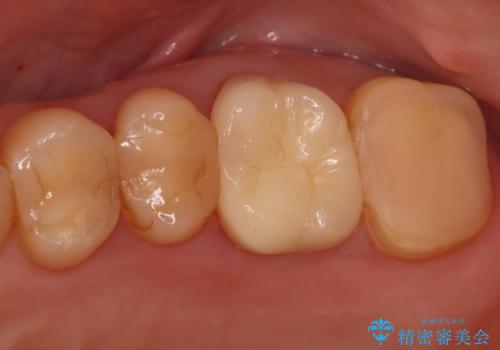

根管治療が完了し、歯の内部が清潔で安定した状態になった後、歯を保護し、強い咬合力に耐えられるよう**クラウン(被せ物)**を装着しました。クラウンは、患者様の希望や咬み合わせの状態に応じて、機能性・審美性に優れた素材を選択し、精密に作製しました。

この一連の治療により、長年の痛みが解消されるとともに、修復した歯の強度と機能が回復。安心して食事を楽しめる奥歯を取り戻していただけました。